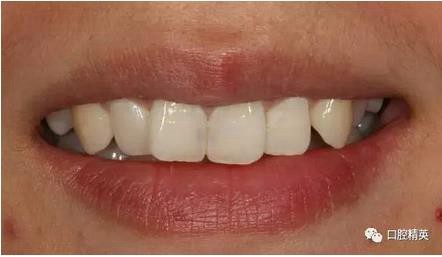

口內(nèi)正側(cè)位及切端特寫

從側(cè)位照可看出遠(yuǎn)中切角略有回收

對(duì)比來看基本達(dá)到患者預(yù)期

有一點(diǎn)不足之處在于齦緣的高低不完全一致,補(bǔ)救辦法同上——激光輕掃